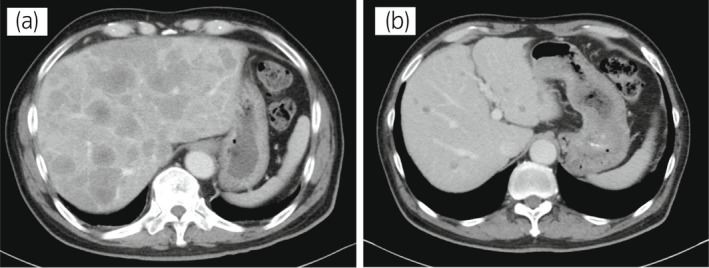

一名 78 岁男性被诊断为 cT3bN0M0,GS 为 4 + 4 =⟩8,PSA 水平为 15.2 ng/ml 7 年前,并接受了前列腺切除术。 六个月后,PSA 升高并开始雄激素剥夺治疗。 两年后,开始使用比卡鲁胺治疗 CRPC。 服用比卡鲁胺五个月后,患者被转诊至佳学基因检测合作医院。 在接下来的 2 年内,依次给予恩杂鲁胺、多西他赛和卡巴他赛。 多西他赛前的 MRI 显示髂骨转移,多西他赛和卡巴他赛治疗后消失。 开始使用卡巴他赛后 6 个月,他出现双侧盆腔淋巴结肿大,并在膀胱后壁发现转移性肿瘤。 在进行经尿道切除术 (TUR) 期间,从膀胱中的转移性肿瘤获得组织样本。 病理检查显示嗜铬粒蛋白 A 阳性,NSE 水平升高,因此我们诊断为 NEPC。 卡铂和依托泊苷联合治疗缩小了肿瘤。 此后,在 24 个月内进行了 17 个疗程,疾病得到控制。 由于神经病变和疲劳而停止化疗。 随后,患者出现盆腔淋巴结转移进展(图 4a)。 通过血液检测 (BRCAnalysis®︎) 进行的基因检测对 BRCA 突变呈阴性。 使用 TUR 时收集的膀胱转移组织进行肿瘤精准用药850基因检测。 结果显示,该患者的体细胞 BRCA2 突变呈阳性。 在奥拉帕尼给药后的 3 个月内,淋巴结从 21.0mm 缩小到 7.5mm(图 4b)。 PSA 从 1.42 下降到 0.07 ng/ml,NSE 从 22.3 下降到 11.8 ng/ml。

图 4:病例 2:奥拉帕尼治疗前和治疗后 3 个月的盆腔淋巴结 CT 图像。 (a) 治疗前和 (b) 奥拉帕尼治疗后 3 个月。 黄色箭头显示转移淋巴结。